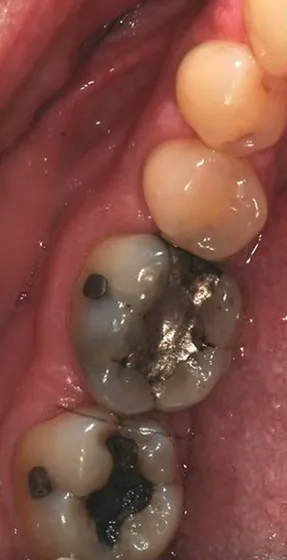

Before

Mercury-Free Dentistry Before and Afters at Suite Dental